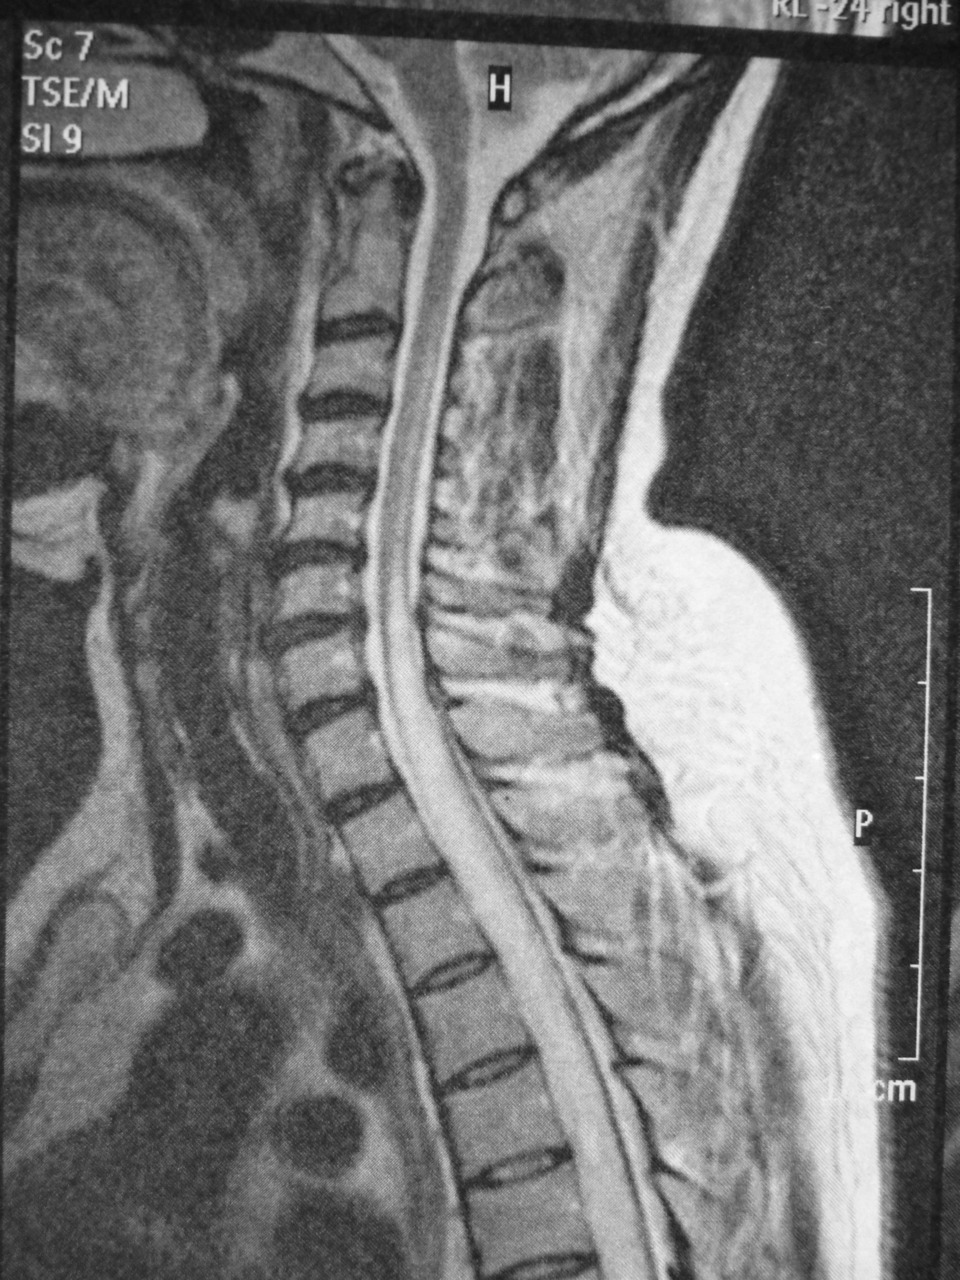

La syringomyélie est une malformation de la moelle épinière pouvant être à l’origine d’une atteinte intramédullaire entrainant des déficits neurologiques de type moteurs, sensitifs et/ou vésico-sphinctériens. En imagerie IRM, l’absence de portion charnue et de signal anormal au sein d’une cavité kystique signe une syringomyélie. C’est un diagnostic différentiel des tumeurs intramédullaires. Les techniques d’intervention sur ce type de malformation ont beaucoup progressé avec l’apport du microscope, du bistouri à ultrasons et du monitorage peropératoire.